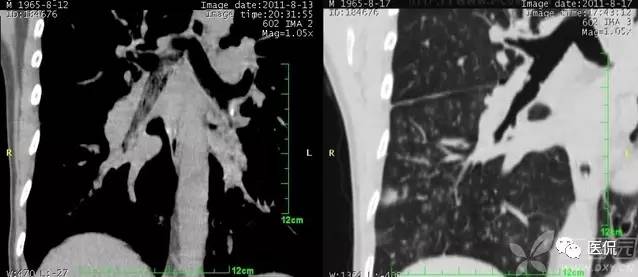

胸腹水鉴别四联症

1、膈肌征:横隔顶向头侧凸出,低密度影在膈外周为胸水,在膈内为腹水。

2、膈脚移位征:胸水时压迫膈脚向前、向外侧移位。

3、界面征:肝与肺在层面上的分界一般是清晰的,腹水时也清晰明确,而当胸水时则肝肺分界不清晰。

4、肝裸区征:肝的背侧内部肝与膈肌直接相贴,此为裸区,产生腹水时液体不在此区潴留。